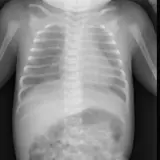

Casos totalmente interactivos con las herramientas que esperaría de un PACS: scroll, ventana, zoom, pan, mediciones, ROI y modo de pantalla completa.

• Anotaciones enlazadas

Anotaciones extensas resaltan los hallazgos clave directamente sobre los casos. Haga clic en los hallazgos enlazados dentro de la descripción del caso para saltar a su ubicación exacta en el estudio.

Desplace, arrastre, ajuste ventana y amplíe como en una estación PACS de trabajo

Aprenda con eficiencia gracias a hallazgos de imagen anotados e ilustraciones